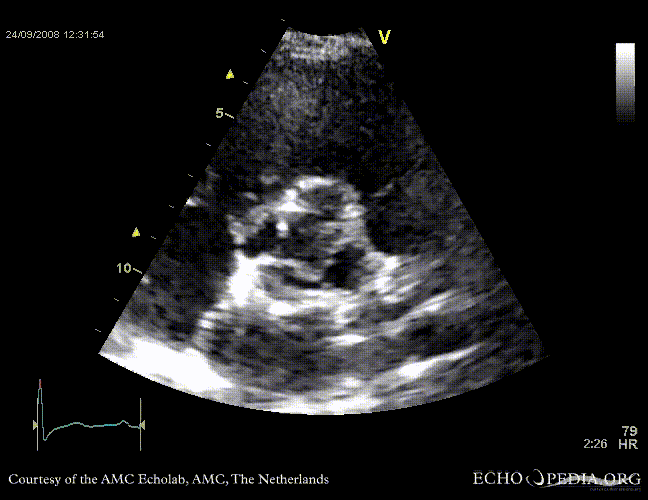

PLAX showing concentric left ventricular hypertrophy PLAX shows aortic regurgitation